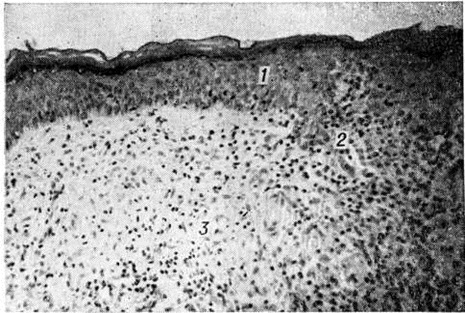

Гистологический исследование биопсийного материала имеет важное значение для установления диагноза и прогноза болезни. Биопсии подвергаются участки поражённой кожи, изредка — поверхностно расположенные нервы. Морфологически изменения при Лепра проявляются в виде гранулем двух полярных типов — лепроматозного (LL) и туберкулоидного (ТТ), а также трёх групп — погранично-туберкулоидной (ВТ), пограничной (ВВ) и погранично-лепроматозной (BL).

Гистологически лепроматозный тип характеризуется лепроматозной гранулемой кожи, которая представляет инфильтрат, расположенный в сетчатом слое, отделённый от эпидермиса непоражённой зоной коллагеновой ткани. Основными клеточными элементами лепроматозной гранулемы являются лепрозные клетки; кроме того, наблюдаются отдельные плазматические, лимфоидные клетки, единичные фибробласты, многоядерные пенистые клетки (цветной рисунок 1—6). Лепрозные клетки относятся к макрофагам, характеризуются бледным ядром и «пенистой» цитоплазмой (рисунок 5) за счёт содержания липидов. Лепрозный макрофаг на ранних стадиях содержит жирные кислоты, фосфолипиды, ненасыщенные липиды; на стадии развития процесса преобладают нейтральные жиры и кислотные липиды. Большинство исследователей считает, что основная масса липидов представляет собой продукт метаболизма и распада микобактерий Лепра. Наиболее характерная особенность лепрозного макрофага — нахождение и размножение в нем большого количества микобактерий Лепра, то есть явление незавершённого фагоцитоза (смотри полный свод знаний). В цитоплазме лепрозной клетки выявляется высокий уровень окислительно-восстановительных ферментов, кислой фосфатазы, неспецифической эстеразы и не обнаруживается активность липазы. Для гистологический картины LL характерно также наличие капилляров со значительным сужением их просвета за счёт пролиферации и набухания эндотелиальных клеток, содержащих большое количество микобактерий типа «глоби». Кожные нервы пронизаны инфильтратами из микробосодержащих клеток (цветной рисунок 7 и 10). Микобактерии обнаруживаются также в клетках эндоневрия. В лепроматозных поражениях большой давности отмечается частичное или полное разрушение придатков кожи (фолликулов волос, сальных и потовых желёз).

При туберкулоидном типе патологический процесса сформировавшийся инфильтрат может быть массивным, занимающим все слои собственно кожи, или располагаться отдельными очагами. Характерно разрушение субэпидермального слоя коллагеновой ткани с расположением гранулемы непосредственно под эпидермисом с эрозированием последнего. Основную массу гранулемы составляют эпителиоидные клетки (смотри полный свод знаний), расположенные в центре и окружённые по периферии валом из лимфоидных клеток (смотри полный свод знаний Лимфоциты), встречаются гигантские многоядерные клетки типа Лангханса (смотри полный свод знаний Гигантские клетки), в небольшом количестве обнаруживаются плазматические клетки (смотри полный свод знаний), тучные клетки (смотри полный свод знаний), фибробласты. В период обострения в гранулеме наблюдается обилие полиморфно-ядерных лейкоцитов (смотри полный свод знаний). Клеточные элементы не содержат микобактерий и липидов. Характерно утолщение нервных стволов за счёт массивной инфильтрации эпителиоидными клетками.

Морфологически структуры, содержащие элементы, характерные для обоих типов Лепра и являющиеся как бы переходной стадией между полярными типами, характерны для пограничной Лепра При недифференцированной Лепра наблюдается картина банального хронический воспаления (смотри полный свод знаний) без специфических изменений. Основными гистологический критериями, определяющими принадлежность к классификационным группам Ридли — Джоплинга, являются следующие морфологический особенности инфильтрата. 1. Клеточный состав гранулемы. В верхней половине спектра (ТТ, ВТ и ВВ) характерно наличие эпителиоидных клеток (цветной рисунок 8) и для ТТ — многоядерных (гигантских) клеток типа Лангханса (цветной рисунок 9). При ВВ эпителиоидные клетки часто отделены друг от друга отёком. В нижней части спектра (BL и LL) эпителиоидные клетки уступают место макрофагам, цитоплазма которых по мере приближения к типу LL становится более плотной, пенистой и содержит жир. 2. Плотность популяций микобактерий. Количество микобактерий возрастает пропорционально от верхней части спектра к нижней. В числовом выражении показатель бактериальной насыщенности лепроматозного инфильтрата для ТТ, ВТ, ВВ, BL и LL составляет 0/1; 0/2,5; 3/4,5; 4/5,5; 5/6,5 соответственно. 3. Количество и топография лимфоцитов в гранулеме. Для ТТ и ВТ свойственно высокое содержание лимфоцитов, расположенных в виде плотного бордюра вокруг массы эпителиоидных клеток. При ВВ и LL количество лимфоцитов чаще снижено, они рассеяны по гранулеме и не образуют вала. 4. Поражение кожных нервов. Для туберкулоидной части спектра характерно значительное утолщение нерва за счёт массивного инфильтрата (повышение максимального диаметра пучка при ТТ). Для ВВ и BL патогномоничны изменения периневрия в виде луковичной кожуры (onion skin) за счёт расслоения его инфильтратом из лимфоцитов, плазмоцитов (при В В) или бактериосодержащих макрофагов (при BL). 5. Отношение к эпидермису. При ТТ и ВТ гранулема располагается непосредственно под эпидермисом и может эрозировать его. При ВВ, BL и LL между инфильтратом и эпидермисом постоянно остаётся непоражённая зона толщиной 30 — 75 микрометров — так называемый слой Ипа, состоящий из коллагеновой ткани.